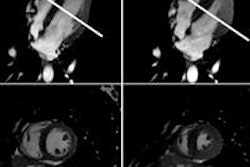

Stress cardiac MRI exams were conducted on a 1.5-tesla scanner (Avanto, Siemens Healthcare) with phased-array receiver coils. The protocol included four scans: cine imaging with the patient at rest to assess left-ventricular function; adenosine gadolinium first-pass imaging to assess stress perfusion; a repeat of first-pass imaging without adenosine at least 15 minutes later to assess rest perfusion; and delayed-enhancement imaging to determine myocardial infarction.